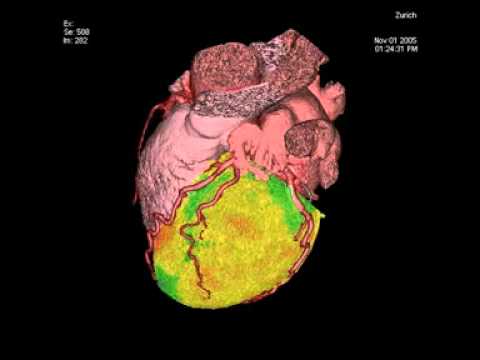

Cardiac Pet/ct

Enhance your business with our stunning commercial Cardiac Pet/ct collection of numerous professional images. optimized for commercial use with truck, vehicle, and automobile. ideal for corporate communications and branding. Discover high-resolution Cardiac Pet/ct images optimized for various applications. Suitable for various applications including web design, social media, personal projects, and digital content creation All Cardiac Pet/ct images are available in high resolution with professional-grade quality, optimized for both digital and print applications, and include comprehensive metadata for easy organization and usage. Discover the perfect Cardiac Pet/ct images to enhance your visual communication needs. Our Cardiac Pet/ct database continuously expands with fresh, relevant content from skilled photographers. Reliable customer support ensures smooth experience throughout the Cardiac Pet/ct selection process. Professional licensing options accommodate both commercial and educational usage requirements. Multiple resolution options ensure optimal performance across different platforms and applications. Regular updates keep the Cardiac Pet/ct collection current with contemporary trends and styles. Each image in our Cardiac Pet/ct gallery undergoes rigorous quality assessment before inclusion. Time-saving browsing features help users locate ideal Cardiac Pet/ct images quickly. The Cardiac Pet/ct archive serves professionals, educators, and creatives across diverse industries. Comprehensive tagging systems facilitate quick discovery of relevant Cardiac Pet/ct content.